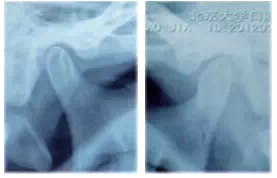

圖9雙側髁突在顳下頜關節(jié)窩內的位置偏后上